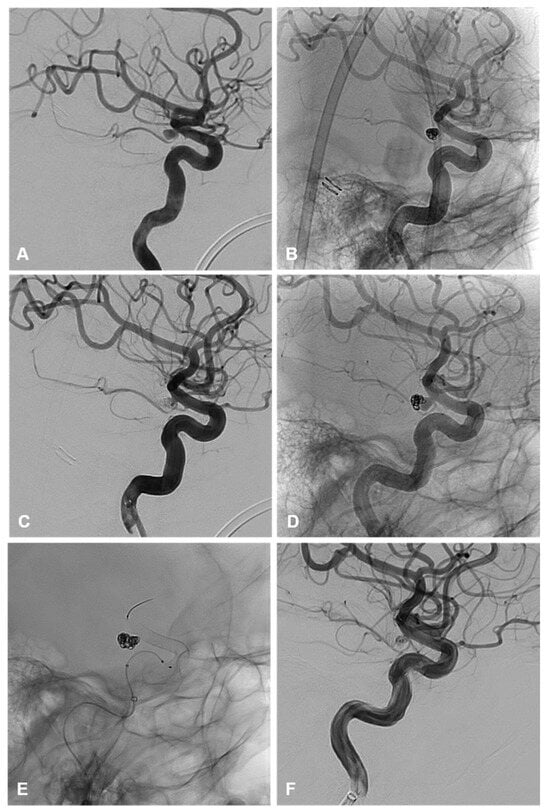

Figure 4. (A) demonstrates a 3D shaded surface display of a ruptured irregular AChoA aneurysm with a posteriorly pointing nipple thought to be the rupture point. Note is made of an additional unruptured aneurysm cranial to this. The patient underwent surgical clipping of the ruptured AChoA aneurysm and remodeling of the neck to preserve the AChoA origin. (B) The patient developed an enlarging residuum on routine surveillance imaging 52 months after initial treatment. This panel demonstrates a 3D shaded surface display of the clip partly obscuring the recurrence. Note is made of the location of both aneurysm necks, which are posterior to the ICA and not visualized adequately from a sub frontal approach. (C,D) are unsubtracted and subtracted lateral angiographic images demonstrating the recurrent AChoA aneurysm and the additional untreated and unruptured aneurysm cranial to this. The patient underwent elective re-treatment with balloon assisted coiling of both aneurysms, the results are seen on the subtracted and unsubtracted angiographic images (E,F). A braided stent was deployed within the ICA, across both aneurysm necks, to promote endothelialization. This is demonstrated on the unsubtracted final angiographic images (G,H).

Within the clipping cohort, 3/7 (43%) patients required endovascular retreatment and 4/7 (57%) patients did not require any further treatment on follow-up. Of those requiring retreatment, 2/3 (66%) were ruptured on initial treatment with clipping and required endovascular retreatment. One patient was an immediate post-clipping residuum requiring primary coiling and the second patient reoccurred after a year and required a combined balloon and stent-assisted coiling. The third patient requiring retreatment was unruptured on initial treatment with clipping and required endovascular retreatment with BAC and FDS. This recurrence occurred >10 years post-clipping and was identified on routine surveillance for additional unsecured intracranial aneurysms.

All recurrences opted for endovascular retreatment with a variety of different endovascular approaches. None of these retreatments required further treatment on follow-up. This preference for endovascular retreatment suggests that the varied armamentarium of endovascular approaches makes it malleable to altered anatomy and possibly less favorable surgical conditions with AChoA aneurysm treatment. This includes the protective micro catheter technique, remodeling with balloons, and reconstructive techniques, using stents and flow diverters. These techniques would be suitable for primary and/or secondary treatment of these aneurysms [3,4,16] (Figure 4).